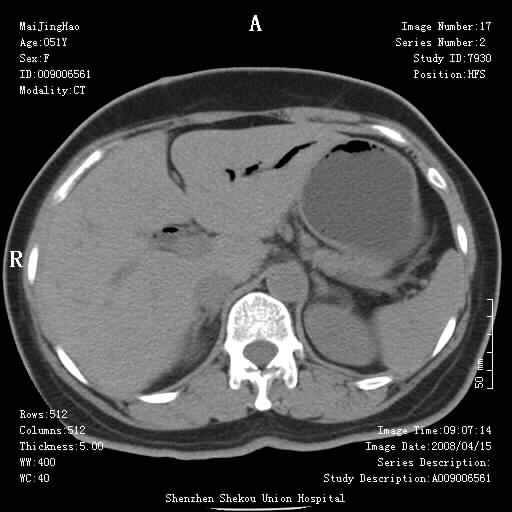

以下是引用余辉在2008-4-26 8:55:00的发言:[br]患者有结石史,此次腹痛4小时,胆总管全程扩张,应有胆总管末端梗阻,此次仍考虑胆结石症,积气不外两种原因,一种是结石下移时肠道内气体逸入,其次为产气菌感染。(倒数第三幅图像于扩张之胆总管末端似可见稍高密度影,考虑为结石影)

以下是引用yangyudong333在2008-4-26 6:17:00的发言:[br]1胆系感染,可能为金葡菌感染,2考虑有化脓性胆管炎致胆总管扩张,3胰头部增大,建议做增强

以下是引用听蝉观竹在2008-4-26 14:21:00的发言:[br]这个病例许多人认为“胰头增大”,那么到底胰头增大的标准是什么呢?

以下是引用听蝉观竹在2008-4-27 10:10:00的发言:[br]关于胰头大小问题有几种测量方法和正常值:[br][br]1、直量法:横径<4cm;[br]2、胰头横径与相邻层面椎体横径的比值为二分之一,超过椎体横径就提示胰头增大;[br]3、正常组成年人肠系膜上动、静脉水平夹角正常值范围为4.9°~34.7°大于35°提示胰头增大。[br][br]上述方法只是一种具体的判断,是“量”的评估,更重要的是“质”的评估:一是观察边缘是否光滑,有无局部隆起,有无分叶;二是观察密度(增强,尤其在动脉期和门脉期)是否均匀。[br][br]所以对于胰头是否有异常不仅仅是是目测可以解决问题的,不要轻易就说“胰头增大”。还有一个问题就是测量胰头应该在增强ct上进行,这样可以避免将血管测量进去。[br][br]为什么啰嗦讲怎么多,因为我们实际工作中同样存在影像科医生和临床医生动不动就说胰头增大,说是胰头癌。大家看看是不是这种情况?[br][br] 我个人观点-----本病例的胰头不增大。[br][br][本贴已被 听蝉观竹 于 2008-4-27 10:12:41 修改过]